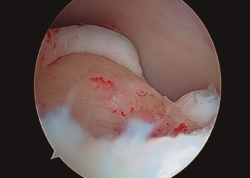

Figura 4. Aspecto final de la membrana de colágeno tapizando completamente el lecho de la lesión.

- Finalmente, procedemos a la colocación de la membrana previa fijación con Tissucol Duo® (sistema adhesivo de fibrina de 2 componentes congelado, tratado por vapor) (Figura 4) y esperaremos 10 minutos hasta comenzar la movilidad del tobillo y comprobar su estabilidad y la ausencia de pinzamiento de la misma.